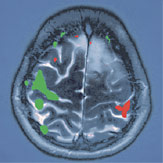

Abb. 2

Mit Hilfe des modernen Navigationssystems kann der Tumor präzis lokalisiert und mit schonender mikrochirurgischer Technik entfernt werden.

Abb. 3

Das vor der Operation angefertigte funktionelle MRI des Schädels stellt die Lage der funktionell wichtigen Gebiete in Bezug zum Tumor dar. Rot markiert ist die Zone der Gesichtsmuskulatur. Während der Operation konnten diese Gebiete mit Hilfe des Neuromonitorings identifiziert und geschont werden.

Vor der Operation wurde eine spezielle MRI-Untersuchung durchgeführt, wobei Sprach- und Körpermotorikzonen identifiziert wurden. Dabei wurde festgestellt, dass der Tumor im hinteren und unteren Bereich an jene Hirngebiete angrenzte bzw. diese verdrängte, welche die Funktion der Fuss-, Hand- und Gesichtsmuskulatur steuern. Eine einfache, nur auf das Tumorgewebe ausgerichtete Entfernung hätte zur Folge gehabt, dass die Patientin nach der Operation eine Lähmung des rechten Fusses und der rechten Hand sowie aufgrund einer Lähmung der Gesichtsmuskulatur erhebliche Mühe beim Kauen und Sprechen davon- getragen hätte – Funktionen, die bis anhin trotz Tumor intakt waren.

Ein Funktionsverlust konnte dank intraoperativem Neuromonitoring vermieden werden: Unter Zuhilfenahme des chirurgischen Navigationssystems sind die Schädeldecke präzise geöffnet und die Tumorgrenzen genau lokalisiert worden. Zuerst wurde eine Elektrokortikographie (eine Hirnstrommessung direkt von der Hirnoberfläche) durchgeführt, wobei festgestellt wurde, dass ein epileptischer Entladungsherd am vorderen, unteren Tumorbereich lag – dieser hatte auch die Krampfanfälle ausgelöst. Mit speziellen Elektroden und Stimulatoren wurden anschliessend die an den Tumorrand angrenzenden Hirngebiete mit ihren funktionswichtigen Arealen identifiziert und die für die Motorik verantwortlichen Zonen – von Fuss, Oberschenkel, Hand, Schulter, Gesicht usw. – mit verschiedenen Nummern markiert. Diese wurden im Verlauf der Operation stimuliert und so fortlaufend überwacht.